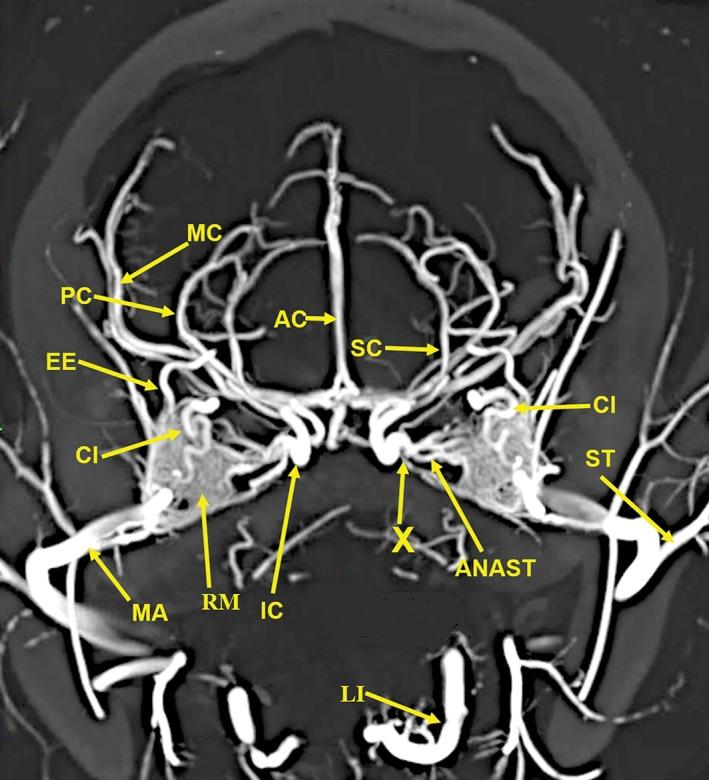

The objective of this study was to investigate the possibility of obtaining high-resolution multiplanar computed tomography (CT) imaging of the cranial arterial circulation of the cat (Felis catus), the rete mirabile, and components of the skull, utilizing preserved cat specimens with an arterial system that was injected with a radiopaque contrast compound in the early 1970s. Review of the literature shows no high-resolution CT studies of the cat's cranial circulation, with only few plain radiographic studies, all with limited cranial vascular visualization. In view of the inability of the radiographic techniques available from 1970s to mid-2000s to provide high-resolution imaging of the arterial circulation within the intact skull and brain of the cat, without dissection and histologic sectioning and disruption of tissues, no further imaging was performed for many years. In 2010, a high-resolution micro CT scanner became available, large enough to scan the entire nondissected head of the arterially injected cats. All the obtained CT images were processed with a software program that provided 3D volume rendering and multiplanar reconstruction with the ability to change the plane angulation and slab thickness. These technical features permitted more precise identification of specific arterial and bony anatomy. The obtained images demonstrated, with a nondestructive method, high-resolution vascular anatomy of the cerebral, orbital, facial arterial system, the rete mirabile, and skull bone components of the cat, with details not previously described in the literature. Anat Rec, 302:1958-1967, 2019. © 2019 The Authors. The Anatomical Record published by Wiley Periodicals, Inc. on behalf of American Association of Anatomists.

本研究旨在探讨利用上世纪 70 年代早期向动脉系统内注入造影剂的保存猫标本,获取猫颅动脉循环、网状血管和颅骨成分的高分辨率多平面计算机断层扫描(CT)成像的可能性。文献回顾表明,目前尚无关于猫颅循环的高分辨率 CT 研究,仅有少数平片研究,但都仅能有限地显示颅血管。鉴于上世纪 70 年代至 2000 年代中期的放射技术无法在不进行解剖和组织学切片及破坏的情况下,提供猫完整颅骨和大脑内动脉循环的高分辨率成像,因此多年来没有进一步进行影像学检查。2010 年,一种高分辨率的微 CT 扫描仪问世,其体积足够大,可以扫描整个经动脉注射的猫的未解剖头部。所有获得的 CT 图像都使用软件进行处理,该软件具有 3D 容积渲染和多平面重建功能,能够改变平面角度和切片厚度。这些技术特征使特定动脉和骨骼解剖结构的识别更加精确。所获得的图像以非破坏性方法显示了猫的大脑、眼部、面部动脉系统、网状血管和颅骨骨成分的高分辨率血管解剖结构,提供了文献中以前未描述过的细节。解剖学记录,302:1958-1967, 2019. © 2019 作者。解剖记录由 Wiley 期刊出版公司代表美国解剖学家协会出版。